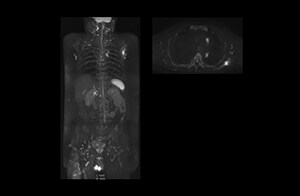

Radiologist Hiroshi Nobusawa, MD, PhD, explains that the coronal DWIBS protocol for whole body DWI is excellent for visualizing lesions in oncology patients. “About 90% of the DWIBS exams are done in this type of patients. The remainder of DWIBS exams are performed to gain information in cases of fevers of unknown origin,” he says. in image acquisition and postprocessing algorithms.”“mDIXON TSE sequences allow simultaneous characterization of morphological changes from the in-phase T2-weighted images and visualization of edematous changes, thanks to the water T2-weighted images from the same acquisition. Anatomical and morphological considerations could be a partial or complete ligament tear, a bony avulsion or hematoma.” “For soft tissue assessment mDIXON brings similar benefits. For example in one T2-weighted mDIXON TSE acquisition, having the multiple contrasts helps us assess abnormalities in peripheral nerves fascicles, which may be due to anatomical or inflammatory changes..” “In peripheral joints, we get good image quality in difficult areas with mDIXON TSE. Fat suppressed images appear homogeneous over the entire image, even with large coverage at 3.0T – for instance in scapular or hip girdles – or in the bearing areas or around metal prostheses*, where fat suppression is often deficient with STIR or spectral fat suppression, causing diagnostic difficulties. If a diagnostic image is right the first time, we don’t need to repeat or add a sequence.” “mDIXON TSE sequences allow simultaneous characterization of morphological changes from the in-phase T2-weighted images and visualization of edematous changes, thanks to the water T2-weighted images from the same acquisition. Anatomical and morphological considerations could be a partial or complete ligament tear, a bony avulsion or hematoma.” “For soft tissue assessment mDIXON brings similar benefits. For example in one T2-weighted mDIXON TSE acquisition, having the multiple contrasts helps us assess abnormalities in peripheral nerves fascicles, which may be due to anatomical or inflammatory changes..”

“The DWIBS sequence’s value in oncology cases is due to the high contrast it creates between lesions and surrounding tissue. Whole body DWI is requested by physicians who need to clarify TNM staging or determine therapeutic strategies, oncologists in need of diagnosis or follow-up scans, surgeons who need to see the presence of distant lesions that are sometimes difficult to detect by CT before surgery, and urologists for the evaluation of bone lesions, and the effect of chemotherapy and radiotherapy.”

After implementing the improved whole body protocol, the radiology team initially did not see a large increase in referrals, although Dr. Nobusawa saw clinical cases where the DWIBS images provided him valuable information for diagnosis. This is why Dr. Nobusawa and Mr. Naka started to actively educate referring physicians about the value of whole body DWIBS. They organized several presentations for physicians in the hospital, where they explained how DWIBS can be of value in oncology patients. The information it provides can be useful for physicians when staging cancer, as well as when determining or adjusting treatment strategy. Mr. Naka remembers some cases where DWIBS provided remarkable information. “In one example, DWIBS visualized bone lesions that could not be seen on PET or SPECT. In another case we had found a bone lesion when a normal L-spine scan for narrowing of the disk space was done. One extra DWIBS scan (2 stations, 8 minutes) demonstrated a lesion that later was confirmed to be the primary region of cancer.”